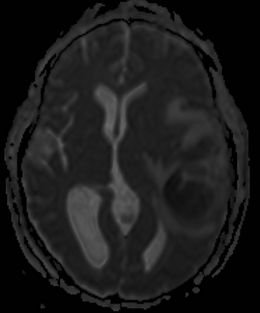

Diffusionsvægtet MR-skanning

DWI ADC

En absces er hvid (White) på DWI (Diffusion Weighted Imaging, det samme som isoB1000) og sort (Dark) på ADC (Apparent Diffusion Coefficent).